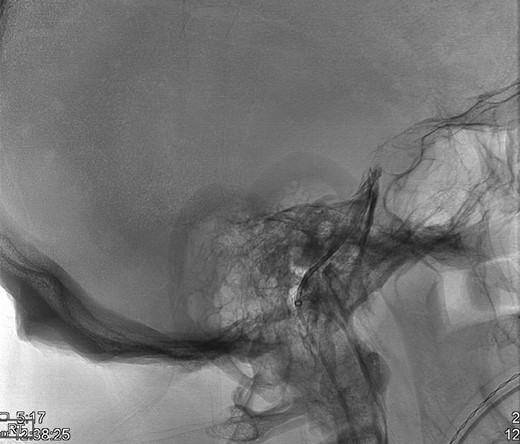

Upon the unimpressive decrease in HbA1C despite an appropriate increase in medical therapy, Cushing’s syndrome was suspected and diagnostic work up was pursued (Fig. 1). A dexamethasone suppression test as well as a late night salivary cortisol test showed abnormal results. The late night cortisol test showed high values congruent with the range necessary for diagnosis of Cushing’s syndrome (>7.5 mcg/dl) [3]. These findings were suggestive of ACTH-dependent Cushing’s syndrome. At this point, an MRI of the brain with sella protocol was ordered and showed no evidence of a pituitary adenoma or pituitary etiology (Fig. 2). Bilateral inferior petrosal sinus sampling was performed (IPSS) and the results were highly suspicious for pituitary microadenoma located more on the left side of the gland, with some activity also present on the right side (Fig. 3). The peak IPSS ACTH value was 1031 pg/ml. A repeat MRI of the brain with sella protocol with higher resolution (3 T MRI with sella protocol with thin cuts) was done in order to visualize the lesion for surgical planning, which did not show any pituitary lesion. FSH, LH, prolactin, insulin-like GF-1, TSH, free T4 and testosterone labs were ordered, and all were within normal limits.